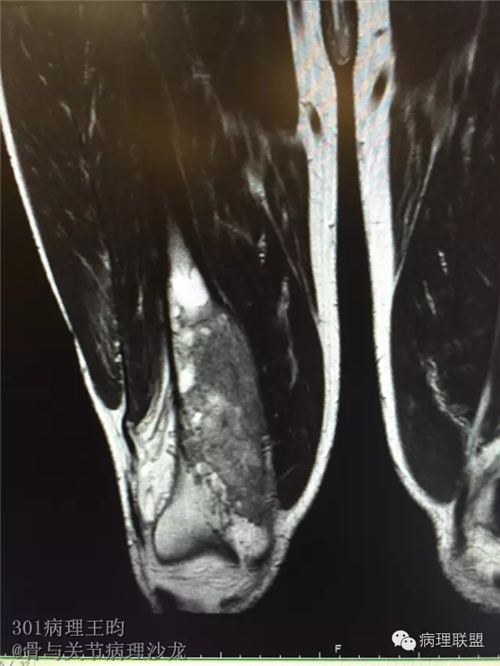

右股骨髓内高分化低级别骨肉瘤or骨纤维异常增殖症(Fibrous Dysplasia)?

男,36岁,活动后疼痛,发现右股骨远端肿瘤。